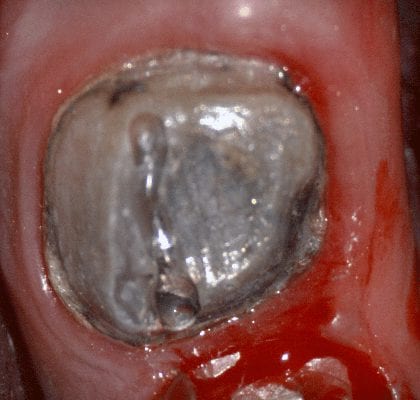

In this video we demonstrate some of the most common problems associated with second molar impressions. Usually the distal margins can be blurred by the presence of hemorrhaging or soft tissue. In this particular case, we use the tip of the camera to displace the tissue and digitall correct an area for better accuracy. The isolite systemisolite systemisolite system does a great job controlling the tongue and the lips and with proper retraction you can image a quadrant in very little time

The second most commong problem is a change in the vertical dimension before and after we prepare the last vertical stop in the arch. We advocate that you take two bites; one before preparing the distal extension and one after you prepare it. Comparing the two buccal bites will let you know if you will have issue with your vertical dimension and allow you to reduce the post op adjustments